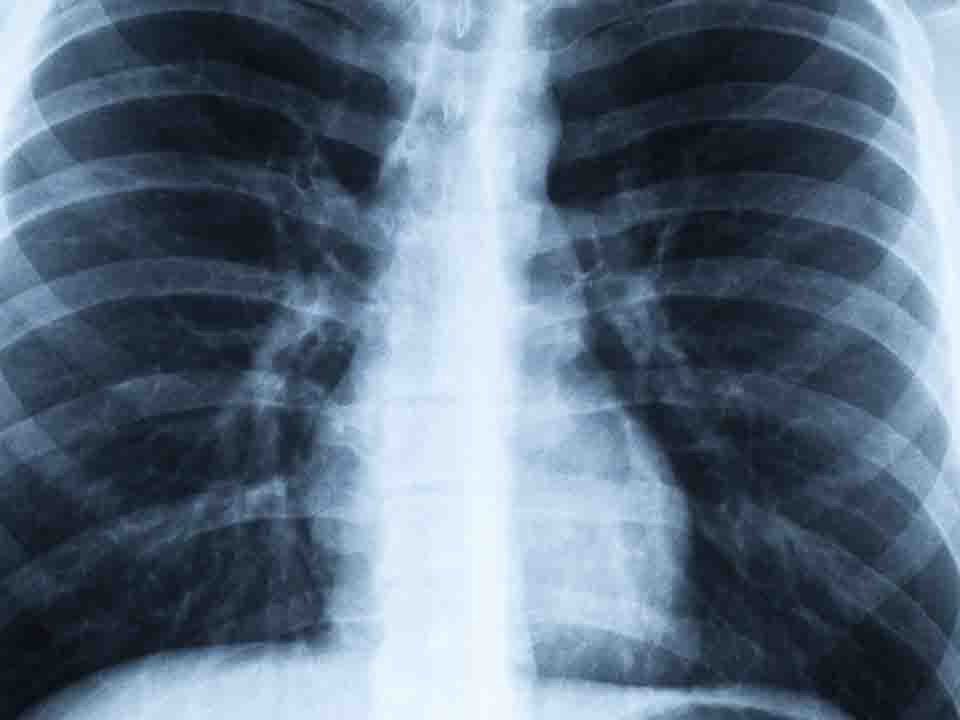

首页 > 生活百科 > 正文 引发毛细支气管炎和肺炎 RSV可导致从轻微感冒到重症肺炎的各种症状 感染特点 并可能累及下呼吸道 (引起毛细支气管炎的主要病因是) 生活百科 2024-12-08 11:51:39 浏览 次 生父 李婷婷 田某某 田某龙 虐待 女童 田田 李婷婷 文某桃 女友 无期 田某某 田某龙 田田 消息资讯 致死案 本文版权声明本文内容由互联网用户自发贡献,该文观点仅代表作者本人。本站仅提供信息存储空间服务,不拥有所有权,不承担相关法律责任。如发现本站有涉嫌抄袭侵权/违法违规的内容,请联系本站客服,一经查实,本站将立刻删除。 上一篇孩子早熟进入青春期年仅八岁父母面临的困惑 下一篇婴幼儿肺炎的高发病毒家长的必知须知婴幼儿